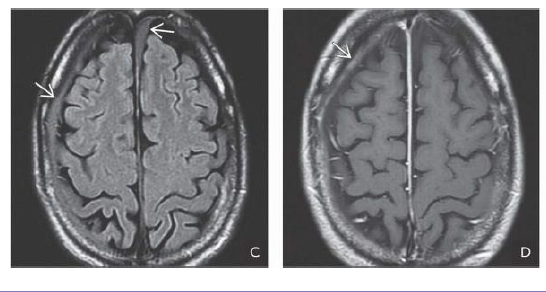

What is the age of the SDH?

The fluid collections do not suppress on FLAIR and are hyperintense to CSF in the underlying

cisterns. 2-37D. T1 C+ shows that the outer membrane of the SDH enhances . Findings are consistent

with late subacute/early chronic subdural hematomas